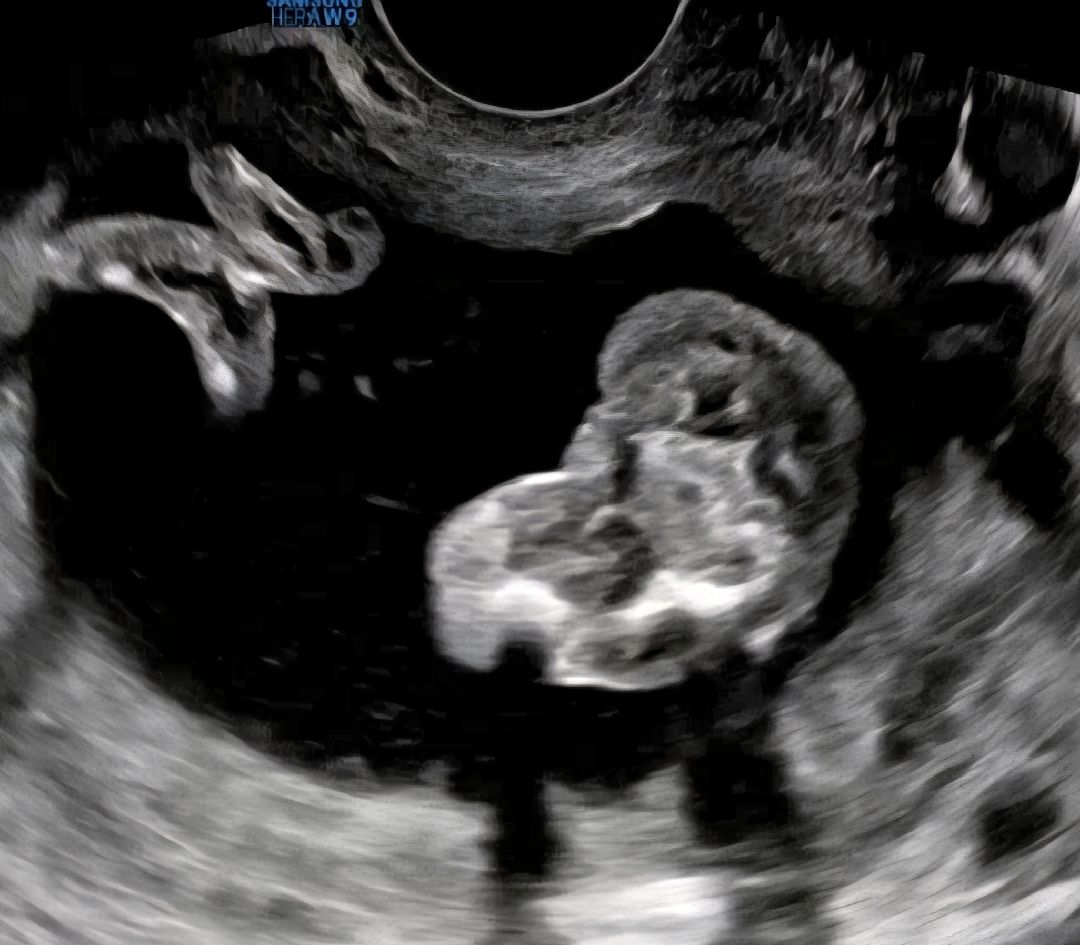

16주 0일 각도법 잘 보시는분

아까 올린거는 배로 본 초음파구요. 쌍둥이인데 ㅠ한명은 확실하게 🌶 가 보이는데 다른애는 다리를 계속 웅크려서 애매하다해서 질 초음파로 봤는데 90프로 딸이라고 하는데 왜 자꾸 뭐가 보이는거 같죠 ㅠ